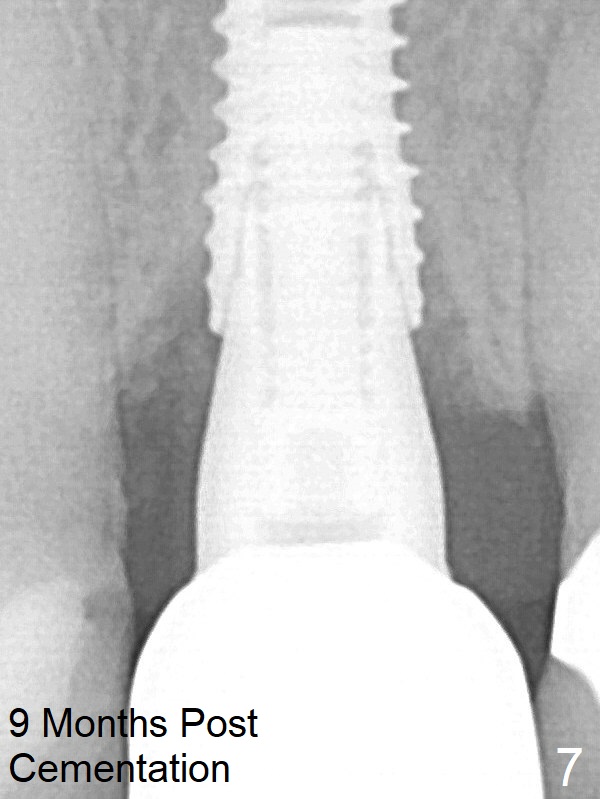

She returns for impression 4 months postop; the abutment margin is substantially subgingival (Fig.6 arrow). The abutment is changed to 4.5x4(4) mm one before impression. There is no bone resorption 9 months post cementation (14 months postop, Fig.7).